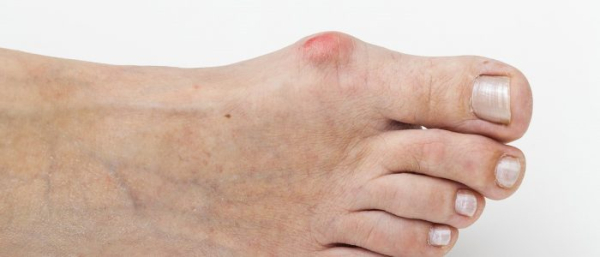

Косточки на большом пальце ноги — очень распространенная проблема деформации ступни с неэстетичным внешним видом. Согласно исследованиям, 98% страдающих наростами больших пальцев ног — женщины. Почему начинается рост новообразования на косточке большого пальца ноги? Нарост на пальце ноги сбоку имеет медицинский термин — вальгусная деформация первого пальца стопы. Недуг на пальцах возникает вследствие неправильного распределения давления на сухожилия при плоскостопии. Нарост на пальце иногда принимают за болезнь, которая называется подагра. Но подагра имеет другую природу происхождения (отложение солей в суставах), и в основном она встречается у мужского пола. Часто подагра встречается на подъеме стопы, где сходятся малая и большая берцовая кость.